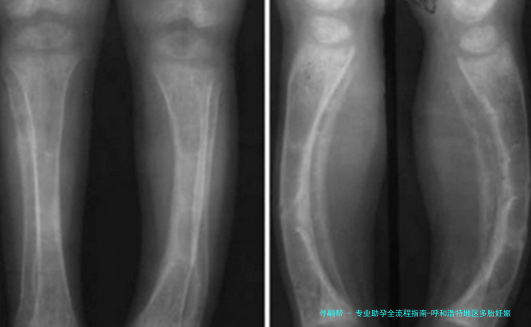

对胎儿来说,多个胎儿妊娠明显增加流产风险(提高5-10倍),导致低出生体重、发育迟缓等问题的发生率明显增高。早产儿各器官发育未成熟,易出现呼吸窘迫综合征、新生儿颅内部出血等多种并发症, *** 妊娠早产儿的死亡率约为单胞胎未足月产儿的2-12倍。

胎儿发育风险早产、低体重、生长受限减胎术、营养支持、卧床休息超声监测生长发育定期产检评估早产风险增加5-10倍